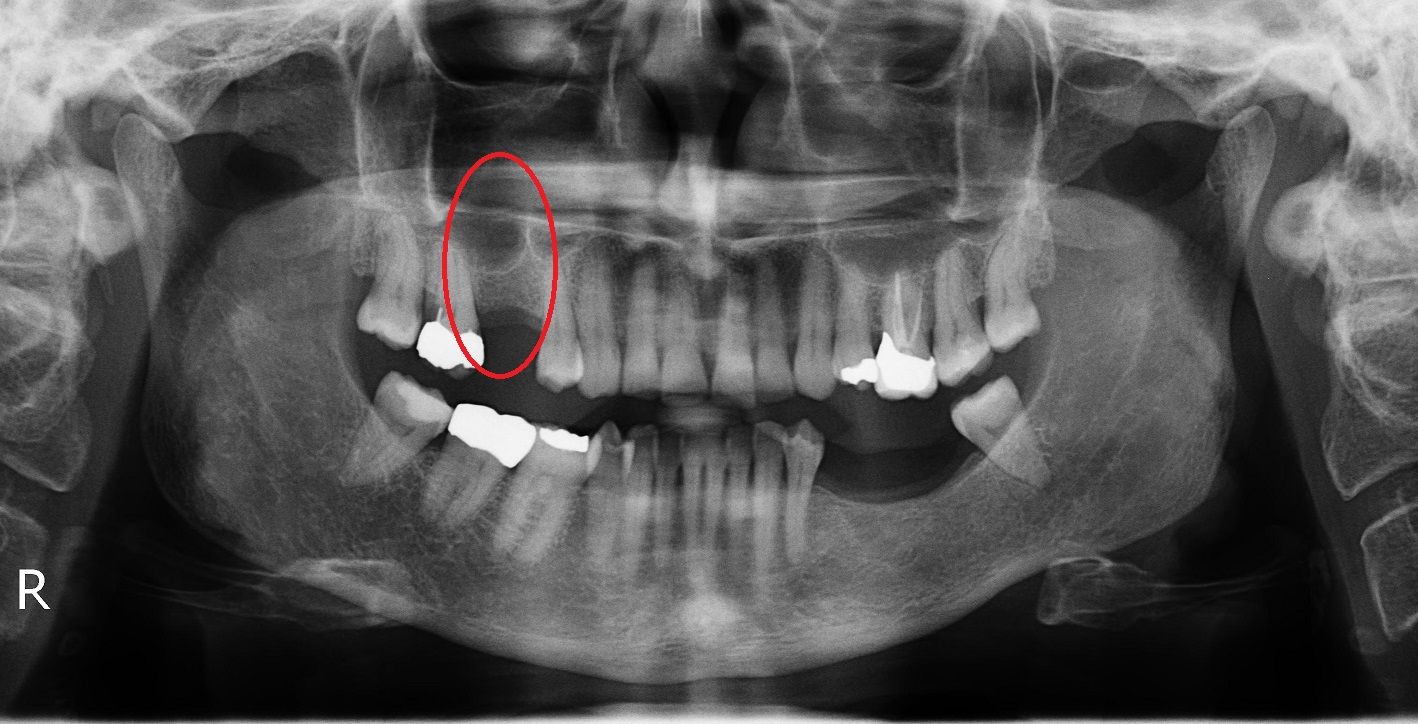

Синус лифтинг

После удаления зуба из-за отсутствия необходимой нагрузки на челюсть, кость в пустующем месте атрофируется. В этом случае перед имплантацией необходимо восполнить объем костной ткани.

Разновидность костной пластики направленной на увеличение объема костной ткани верхней челюсти в районе гайморовых пазух.

Открытый синус лифтинг

Открытый синус-лифтинг применяется, когда для установки имплантата не хватает более 3 мм костной ткани. При проведении этой операции имплантация в ряде случаев возможна только после полного восстановления кости челюсти.

Закрытый синус лифтинг

Закрытый синус-лифтинг подходит для наращивания небольшого объема костной ткани (1-3 мм). Он менее травматичен, чем открытый. Подсадка костного материала проводится через небольшое отверстие для имплантата.

При закрытом типе синус-лифтинга имплантация проводится сразу. Вам не придётся лишний раз посещать стоматолога.

• до синус-лифтинга

• после синус-лифтинга

• после установки имплантатов в верхнюю челюсть

• коронки установленные на имплантаты